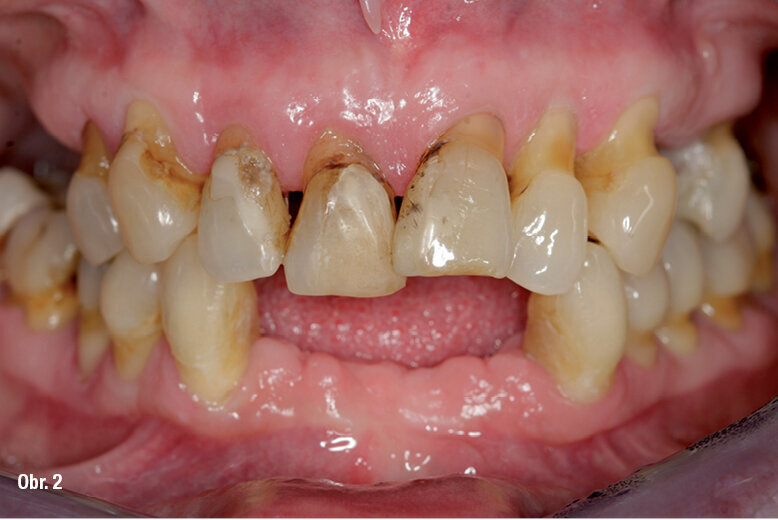

53letá pacientka se dostavila do naší praxe s dotazem, zda v jejím případě existují nějaké možnosti fixní zubní náhrady. Její dosavadní lékařka jí oznámila, že všechny zbývající zuby se musí kvůli špatnému stavu parodontu extrahovat (obr. 1). Zubní lékařka již vyrobila horní a dolní celkovou protézu jako imediátní náhradu. V rámci akutního zubního ošetření musely být při první konzultaci v naší praxi extrahovány čtyři dolní řezáky kvůli silnému stupni viklavosti (obr. 2) a nasazena imediátní náhrada těchto zubů.